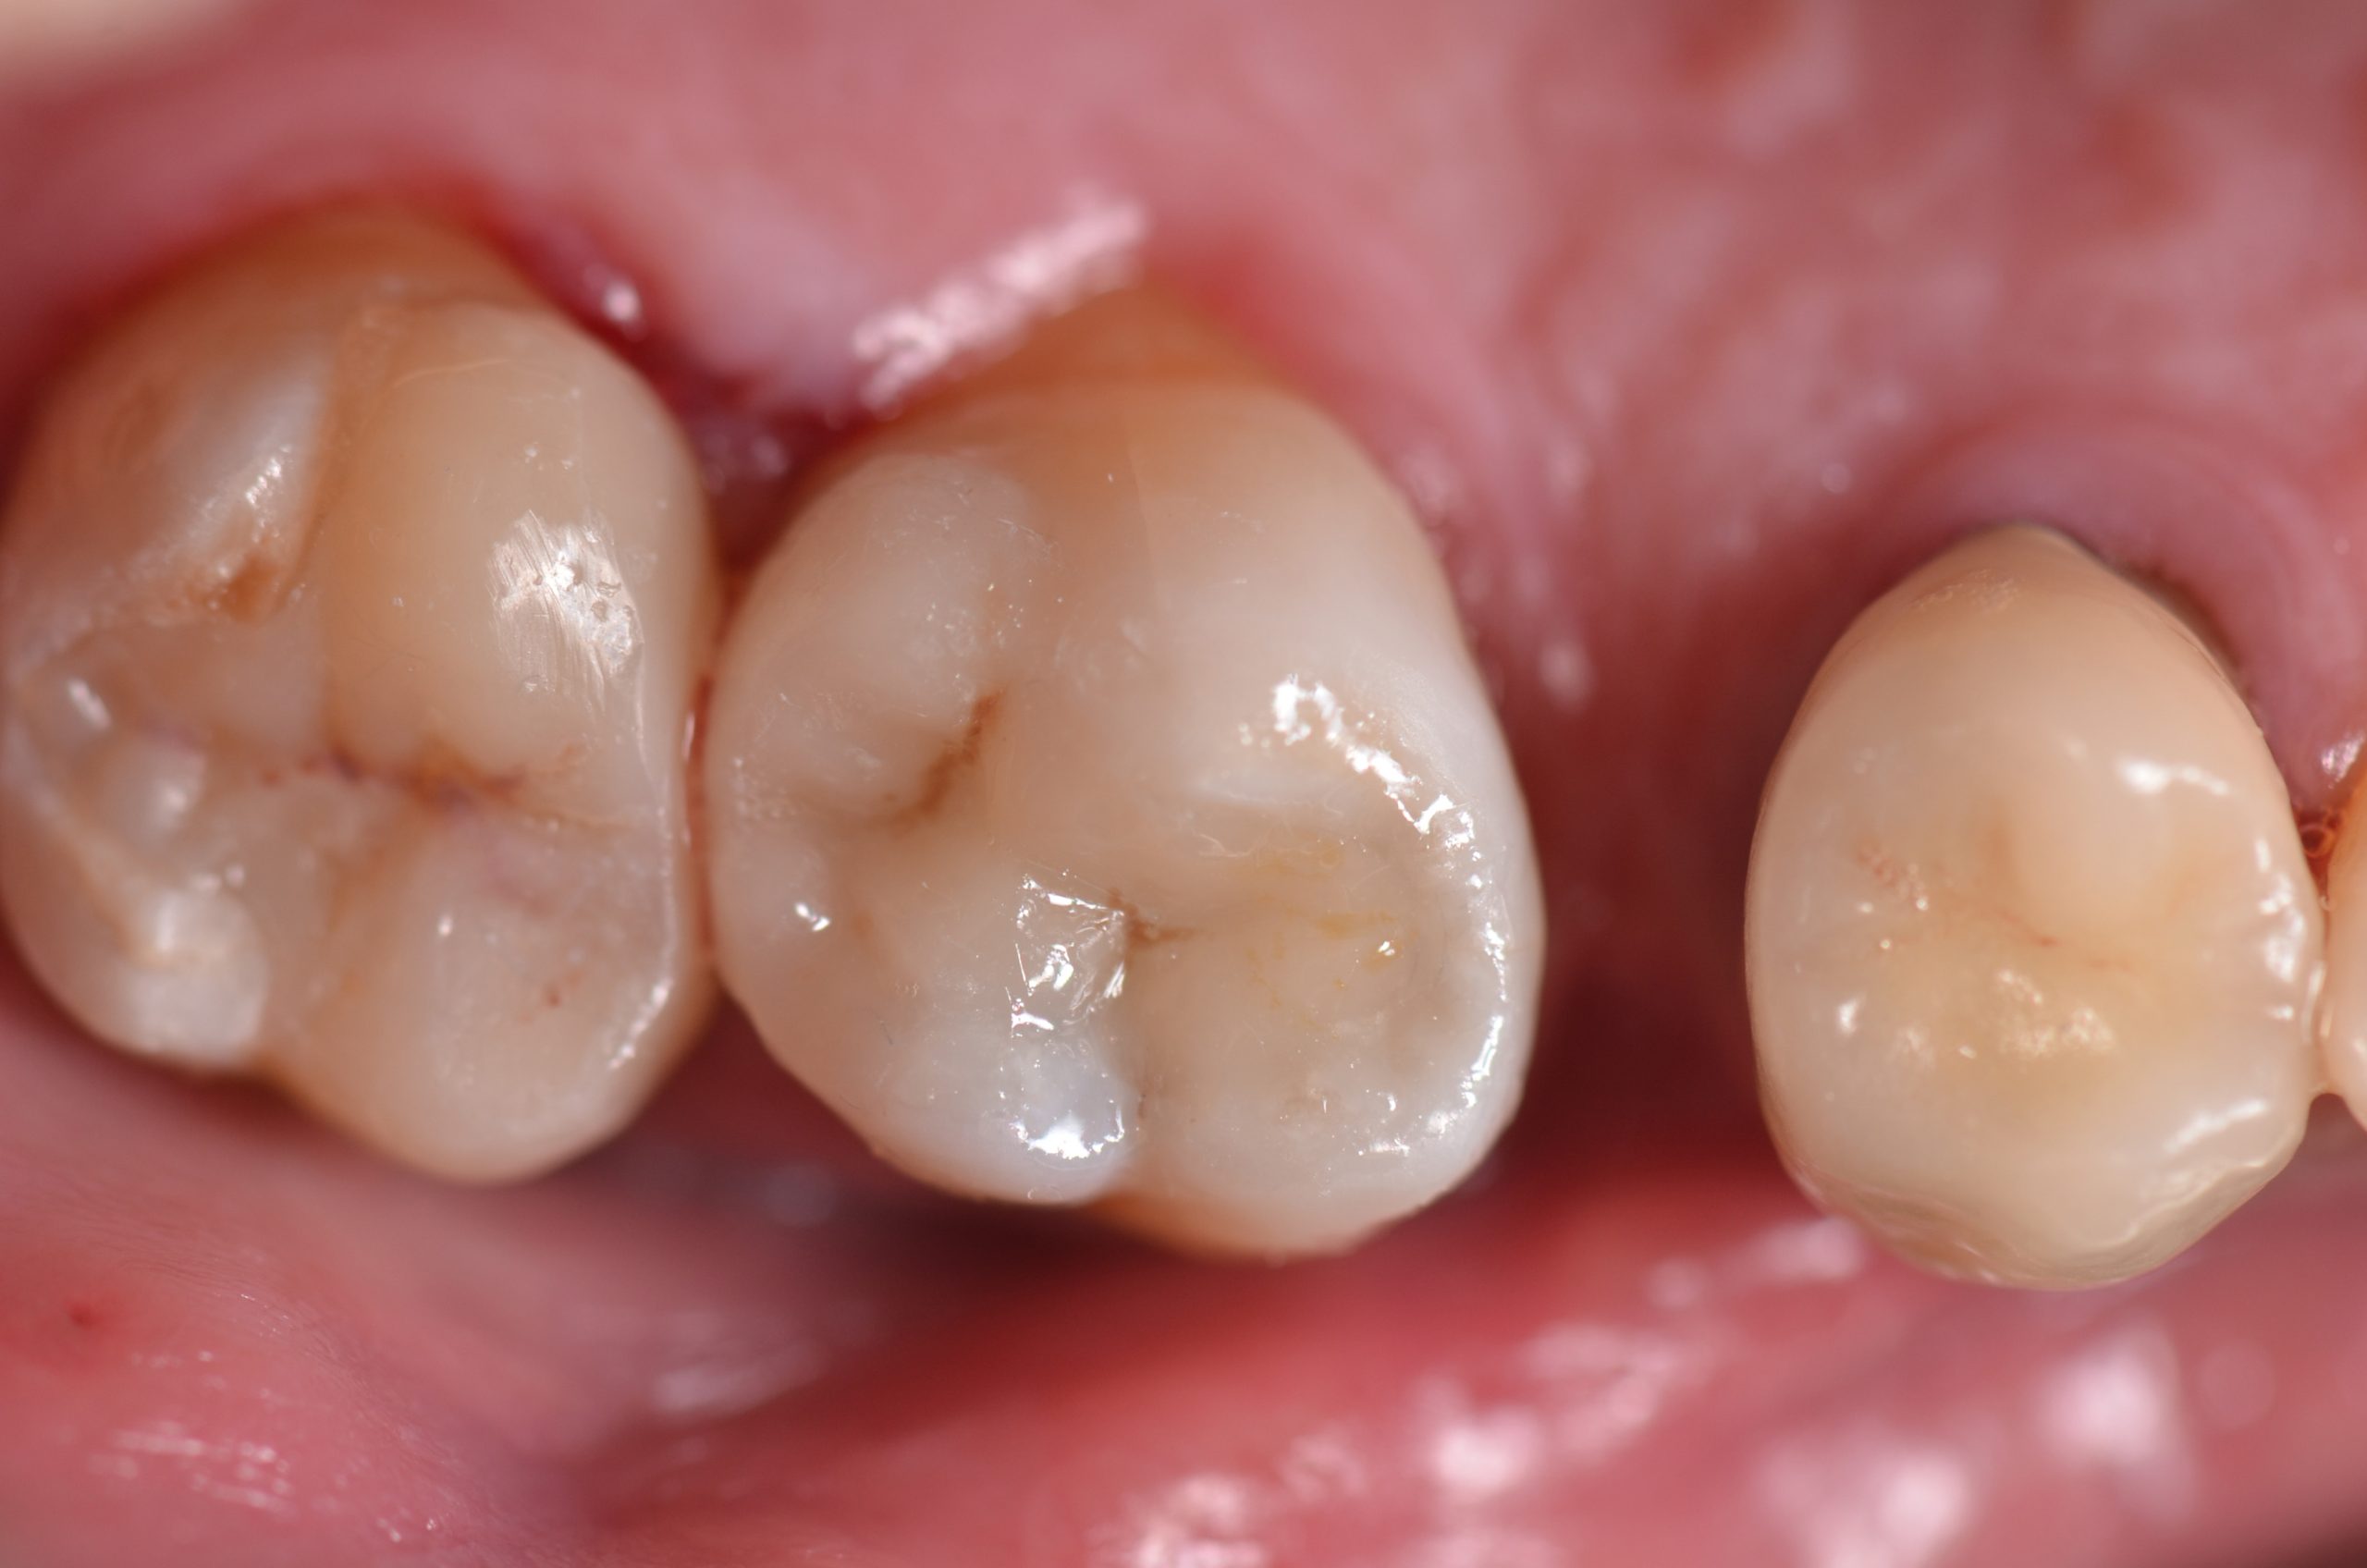

Una paziente di 44 anni si presenta alla nostra attenzione per la sostituzione di un vecchio restauro danneggiato. All’esame clinico si osserva la frattura della cuspide disto-palatina dell’elemento 1.6, associata a infiltrazione marginale di un restauro in composito incongruo. Le radiografie periapicali non evidenziano radiotrasparenze periapicali, ma mostrano possibili aree di demineralizzazione in zona marginale e all’interfaccia dente-restauro (1, 2, 3) (Figure 1-2).

Rifinitura e lucidatura dei restauri

Dopo la rimozione della diga di gomma, per le zone di contatto si procede a rifiniture interprossimali con strisce abrasive. Concluso il controllo occlusale, per il molaggio selettivo dei precontatti si utilizza una fresa a pallina in carburo di tungsteno. Seguono quindi rifinitura e lucidatura con gommini abrasivi diamantati. Alcune superfici ruvide dell’overlay vengono rifinite e lucidate con l’ausilio di dischetti abrasivi a grana fine e di gommini. Con i dischi in feltro si passa alla lucidatura a specchio impiegando una pasta non abrasiva all’ossido di cerio. Dopo 15 giorni, si eseguono controllo radiografico e verifica del restauro eseguito (Figure 16-18). La Tabella 1 riassume il protocollo clinico utilizzato in questo case report.